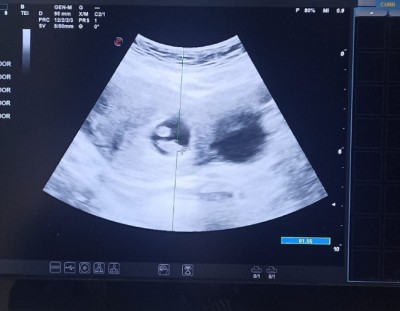

Doktorum tek dedi ama ikinci bir kese var gibi duruyor sizce tek mi çift mi kızlar

Gebelik haftası 7+5

Bnede de aynısı olmuştu iki tane kese var gibi göründü ama biri gaz biri bebkmiş

Sende de aynısı maşallah birinde bebek var

Diğeri de gaz

Bnce ikiz değil

İkiz olsa o kesede de bebek görunurdu

Kese olsaydı doktor söylerdi diye dusunuyorum ama hayirlisi olsun. Arkadasin dedigi gibi gaz da olabilir kistte olabilir benim bir onceki gebeligimde ilk haftalarda kist cikmisti boyle doguma kadar kaybolmustu bir zarari yok yani eger oyleysede